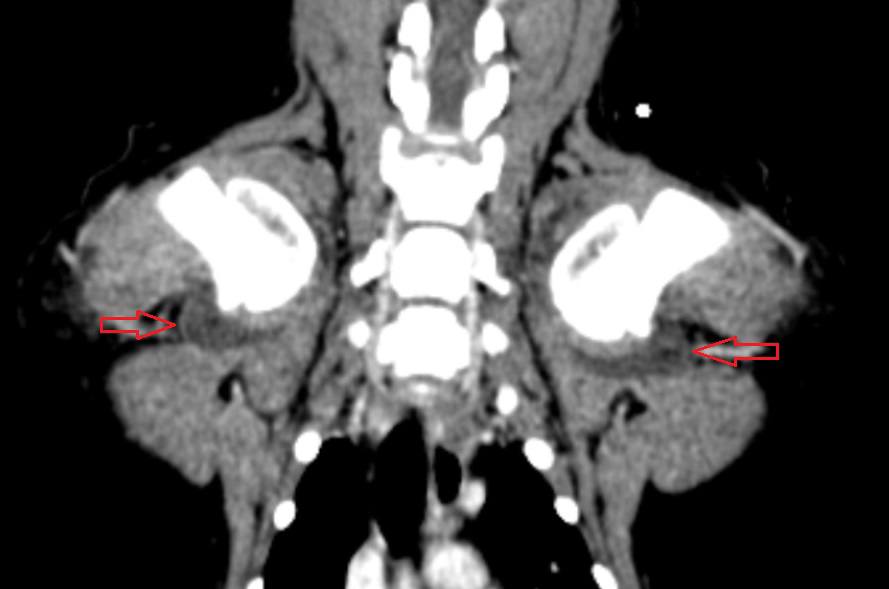

Все фторхинолоны, включая левофлоксацин, могут вызывать артропатию у молодых животных6. Считается, что среди экспериментальных животных, таких как мыши, крысы, морские свинки, кролики, собаки и нечеловекообразные приматы, молодые собаки (как правило, крупных, быстрорастущих пород6) в возрастной группе 4–28 недель наиболее восприимчивы к артропатии, вызванной хинолонами6-7. Участки повреждения, наиболее подверженные макроскопическим изменениям, согласно некоторым исследованиям, – дорсальная область головок плечевой и бедренной костей, а также зоны вокруг места прикрепления круглой связки (рис. 1).

Была проведена повторная КТ с внутривенным контрастированием, по результатам которой было выявлено значительное увеличение размеров капсул в обоих плечевых (рис. 3, 4), локтевых и тазобедренных суставах, а также в левом коленном суставе по сравнению с данными первоначального КТ-исследования.

На основании клинических симптомов, анамнеза приема левофлоксацина, отсутствия ортопедических симптомов до поступления пациента в клинику, результатов анализов крови и синовиальной жидкости, а также проведенной КТ был поставлен диагноз «множественная артропатия, вызванная применением фторхинолонов».